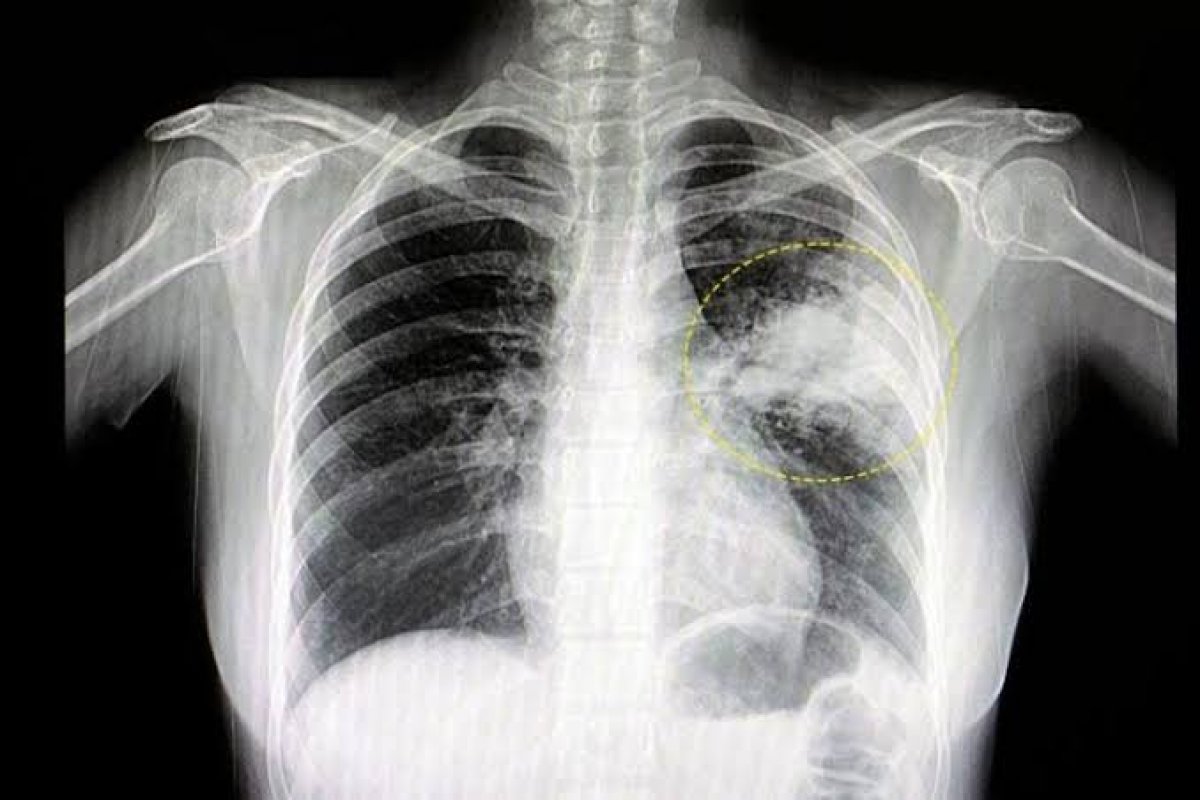

Dados da Secretaria de Saúde do Estado Bahia (Sesab) mostram que 2.309 baianos morreram em decorrência da pneumonia até julho deste ano. Ainda segundo o órgão, em 2022, foram 4.009 óbitos. O cenário reforça a importância do cuidado com a doença, que é a principal causa de morte em crianças de até 5 anos de idade, conforme a Sociedade Brasileira de Pneumologia e Tisiologia (SBPT). Com isso, em função do Dia Mundial da Pneumonia, lembrado em 12 de novembro, se alerta para os riscos da doença que ataca os pulmões, podendo ser adquirida pelo ar, saliva, secreções, transfusão de sangue ou, na época do inverno, devido à mudança brusca de temperatura.

Segundo a médica, a pneumonia afeta principalmente os pulmões que, ao serem inflamados, se enchem de pus e líquido. Ela indica também que os sintomas variam de acordo com a faixa etária. “De modo geral, os sintomas são febre, tosse, dificuldade para respirar e mal estar. Os casos podem evoluir com maior gravidade”, observa.